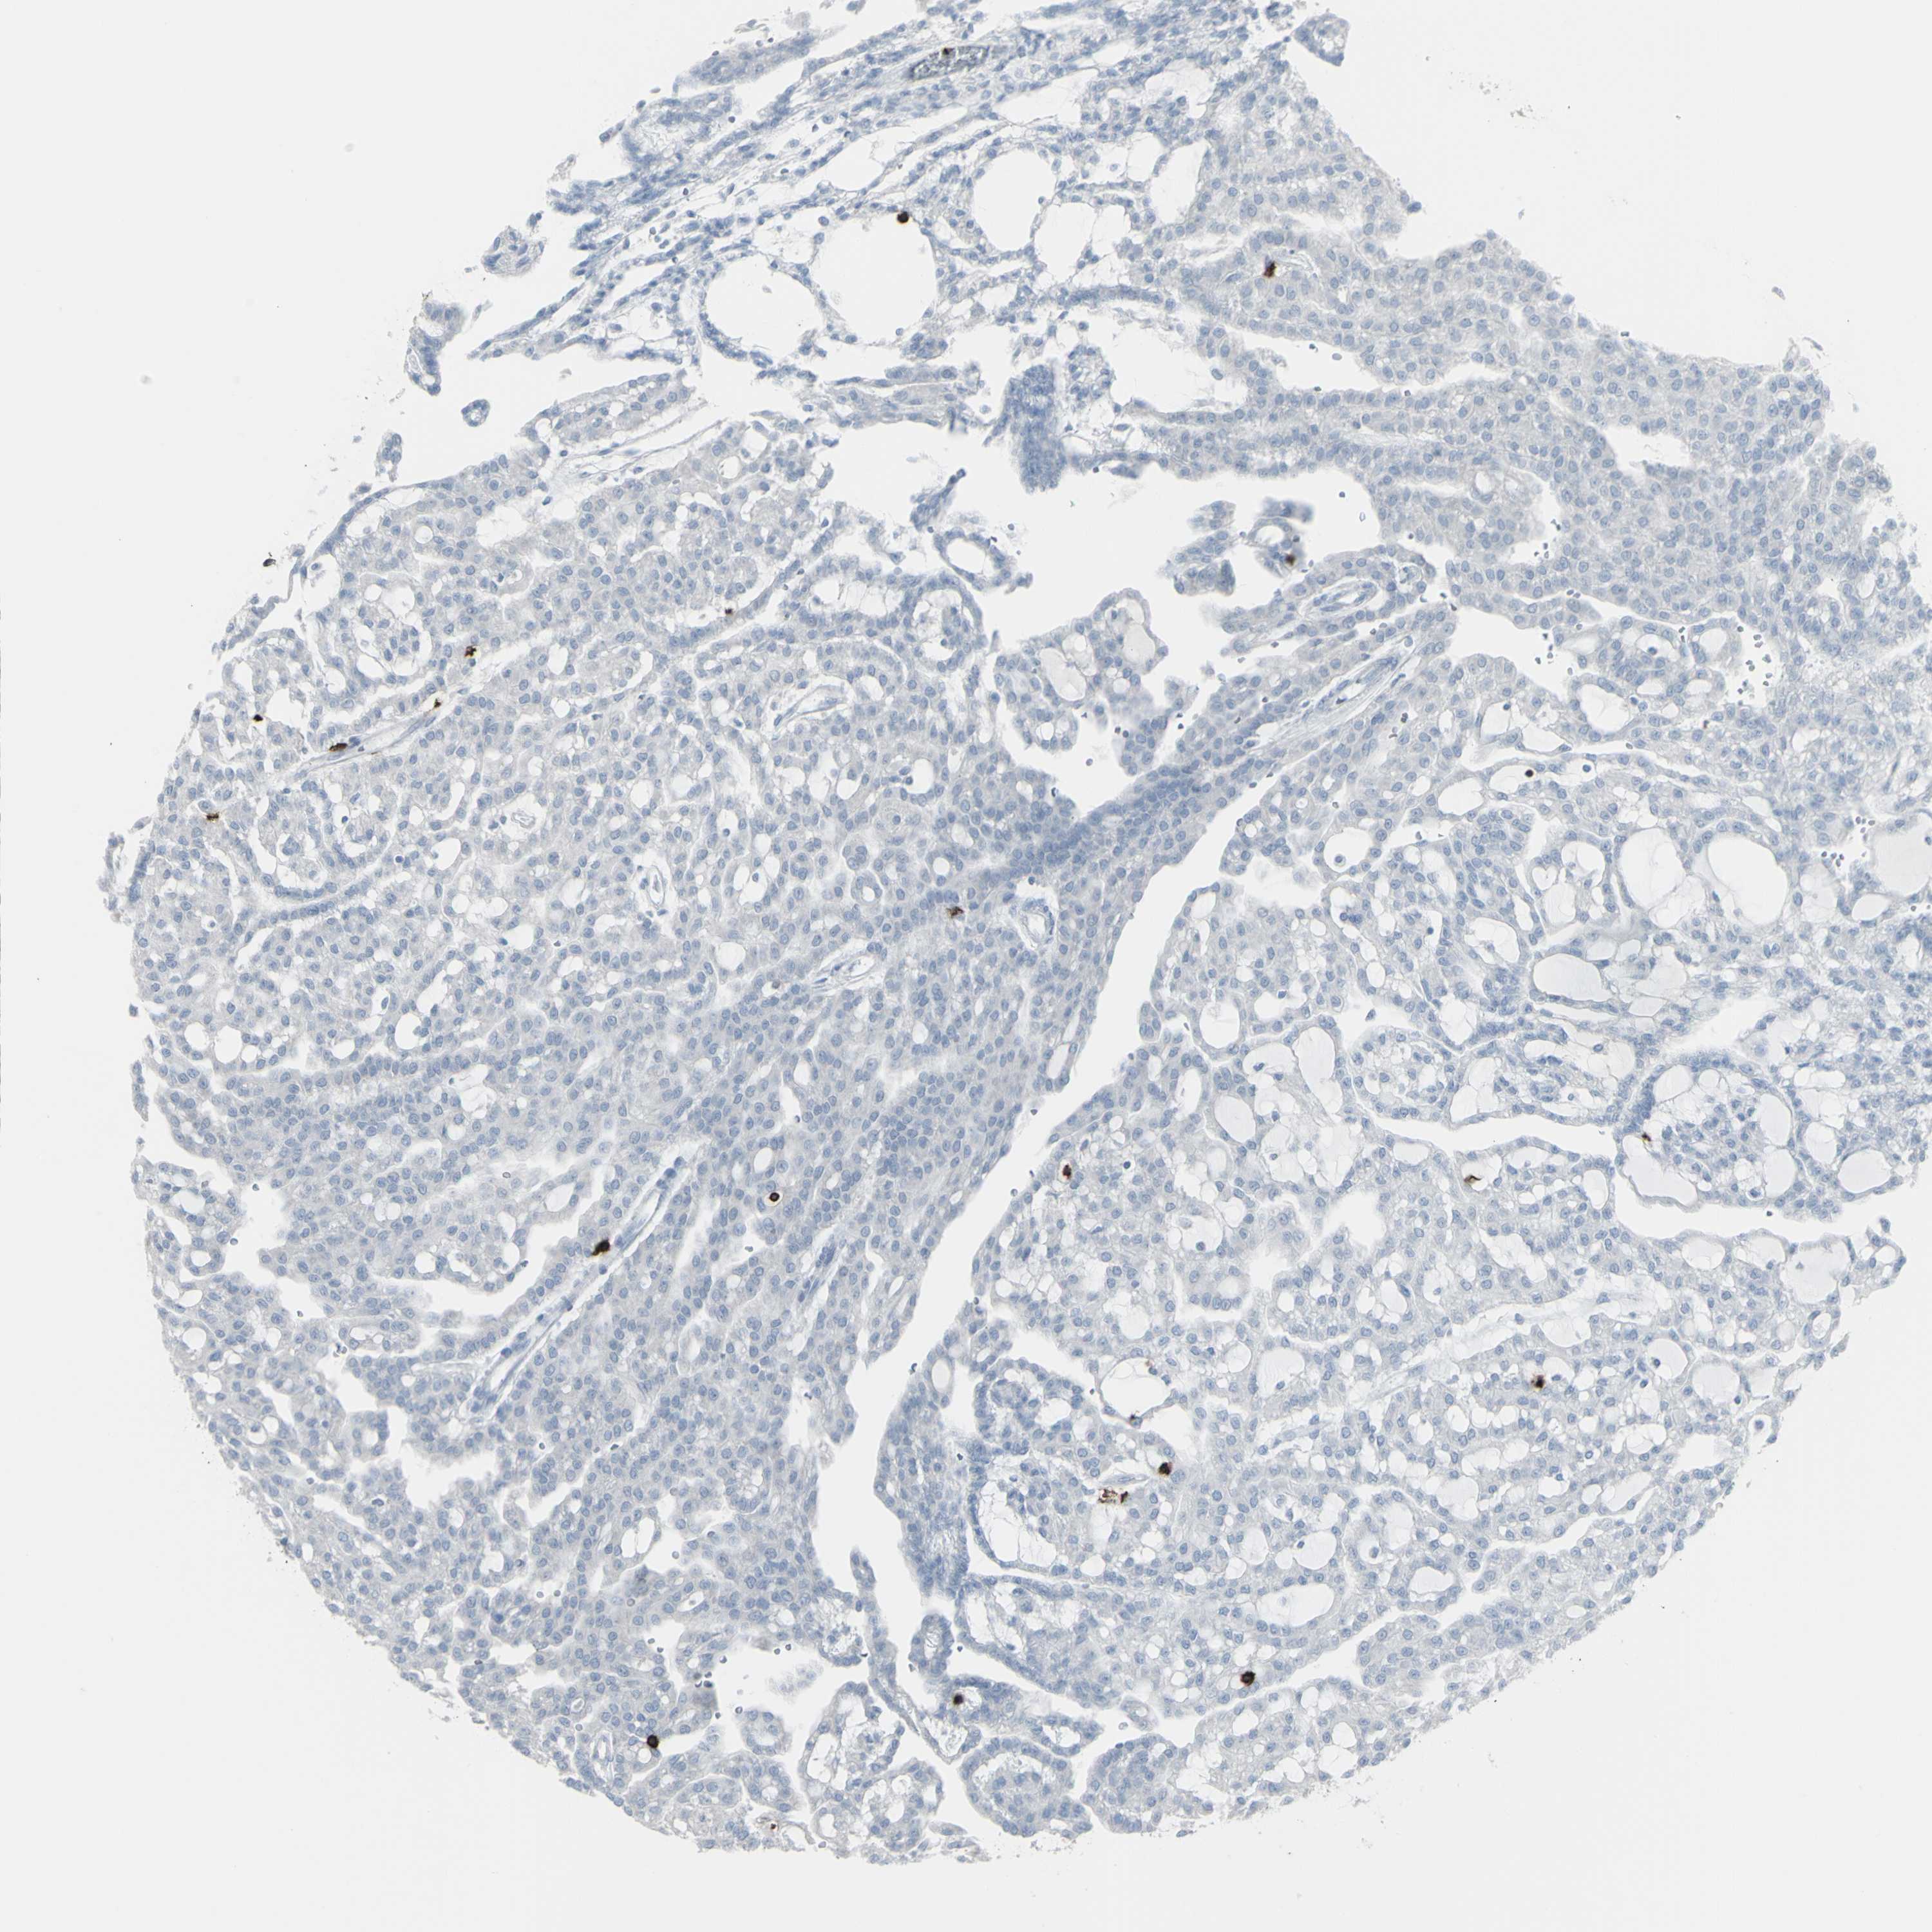

KIDNEY RENAL PAPILLARY CELL CARCINOMA (TCGA) - Interactive survival scatter ploti

The Survival Scatter plot shows the clinical status (i.e. dead or alive) for all individuals in the patient cohort, based on the same data that underlies the corresponding Kaplan-Meier plots. Patients that are alive at last time for follow-up are shown in blue and patients who have died during the study are shown in red.

The x-axis shows the expression levels (FPKM) of the investigated gene in the tumor tissue at the time of diagnosis. The y-axis shows the follow-up time after diagnosis (years). Both axes are complimented with kernel density curves demonstrating the data density over the axes. The top density plot shows the expression levels (FPKM) distribution among dead (red) and alive patients (blue). The right density plot shows the data density of the survived years of dead patients with high and low expression levels respectively, stratified using the cutoff indicated by the vertical dashed line through the Survival Scatter plot. This cutoff is automatically defined based on the FPKM cutoff that minimizes the p-score. The cutoff can be changed by dragging the vertical line or by entering a cutoff value in the square labeled "Current cut-off".

Under the Survival Scatter plot the p-score landscape (black curve; left axis) is shown together with dead median separation (red curve; right axis). Dead median separation is the difference in median mRNA expression between patients who have died with high and low expression, respectively. It is calculated as follows: median FPKM expression of dead patients with high expression - median FPKM expression of dead patients with low expression. This is intended to aid the user in visually exploring custom cutoffs and the associated p-scores and dead median separation.

Individual patient data is displayed and can be filtered by clicking on one or more of the category buttons on the top of the page. Categories describing expression level and patient information include: high, low, alive, dead, female, male and tumor stages. The scale of the x-axis can be toggled between linear and log-scale by clicking on the "x log" button. Mouse-over function shows TCGA ID, patient information and mRNA expression (FPKM) for each patient.

& Survival analysisi

Kaplan-Meier plots summarize results from analysis of correlation between mRNA expression level and patient survival. Patients were divided based on level of expression into one of the two groups "low" (under cut off) or "high" (over cut off). X-axis shows time for survival (years) and y-axis shows the probability of survival, where 1.0 corresponds to 100 percent.

CD247 is not prognostic in Kidney Renal Papillary Cell Carcinoma (TCGA)

Best expression cut offi

Based on the FPKM value of each gene, patients were classified into two groups and association between prognosis (survival) and gene expression (FPKM) was examined. The best expression cut-off refers the FPKM value that yields maximal difference with regard to survival between the two groups at the lowest log-rank P-value. Best expression cut-off was selected based on survival analysis .

When clicking on this number, the vertical dashed line indicating cut-off, the interactive survival plot, and the Kaplan-Meier curve will be adjusted to show results based on the best expression cut-off.

: 3.06